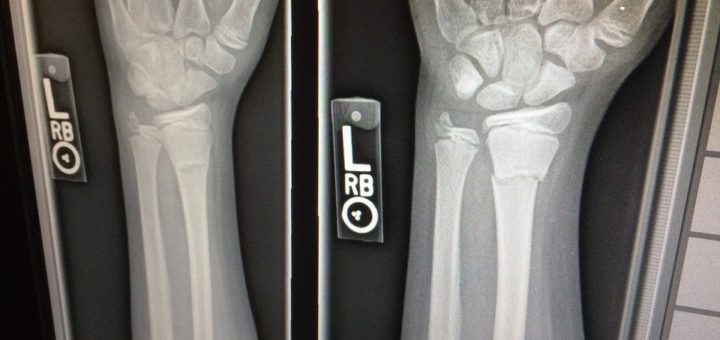

Osteoporoza – ko se kosti lomijo

Osteoporoza, ki dobesedno pomeni porozne kosti, je bolezen, zaradi katere kosti postanejo krhke in posledično bolj lomljive. Osteoporoza, ki poteka brez kliničnih znakov, zaradi česa si je prislužila naziv “nema bolezen”, ima okrog 80...